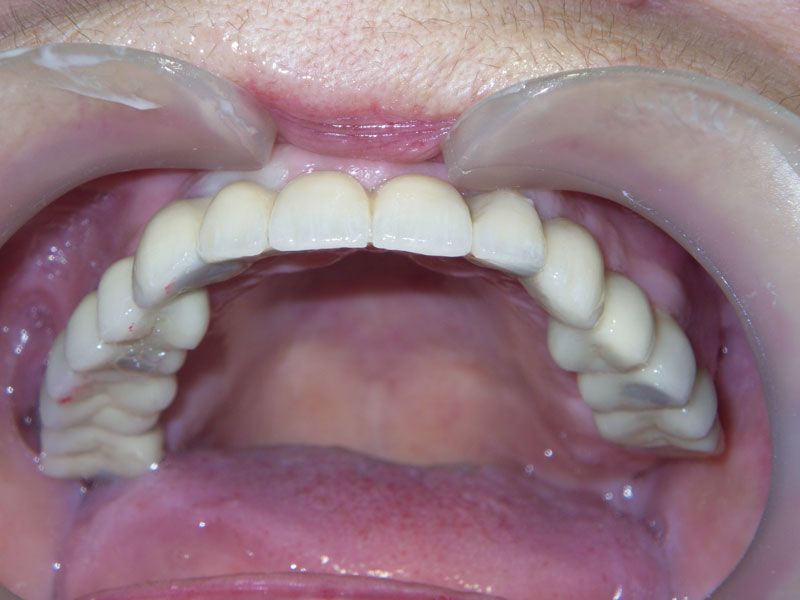

Протезирование было проведено с помощью трех мостовидных протезов, причем выбор цвета и формы зубов был предоставлен пациенту. Оказалось, что высоко-эстетичнын зубы, были мечтой пациентки всю жизнь. Они и были выбраны. Диссонанс с собственными зубами, которыми так дорожила наша пациентка до операции, оказался столь сильным, что теперь в планах пациентки заняться нижней челюстью в плане функционально-эстетическойй реабилитации фронтального участка несъемным протезированием на имплантах.